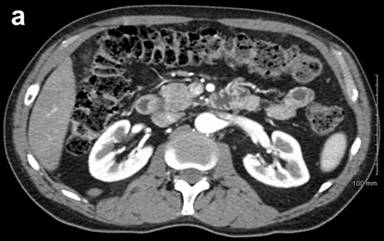

A previously healthy, non-diabetic 56-year-old man presented in March 2010 with abdominal pain and nausea to an outside facility. Following an extensive workup, including imaging, he was diagnosed with chronic pancreatitis. Repeat CT, one year later on re-presentation with jaundice, demonstrated an atrophic pancreas and a 3 cm hypodense area in the tail of the pancreas with splenic vein invasion as well as a second mass of 2 cm in the head of the pancreas with invasion of the portosplenic confluence (Figure 1). Endoscopic ultrasound with fine-needle aspiration confirmed the presence of both masses with the pancreas head lesion being concerning for invasion into the splenoportal vein confluence (Figure 2). Biopsy of the head mass demonstrated undifferentiated carcinoma with osteoclast-like giant cells. Based on these findings, diffuse involvement of the entire gland with neoplastic process was suspected.

Figure 1. a. Pancreatic head mass. b. Pancreatic tail mass. |